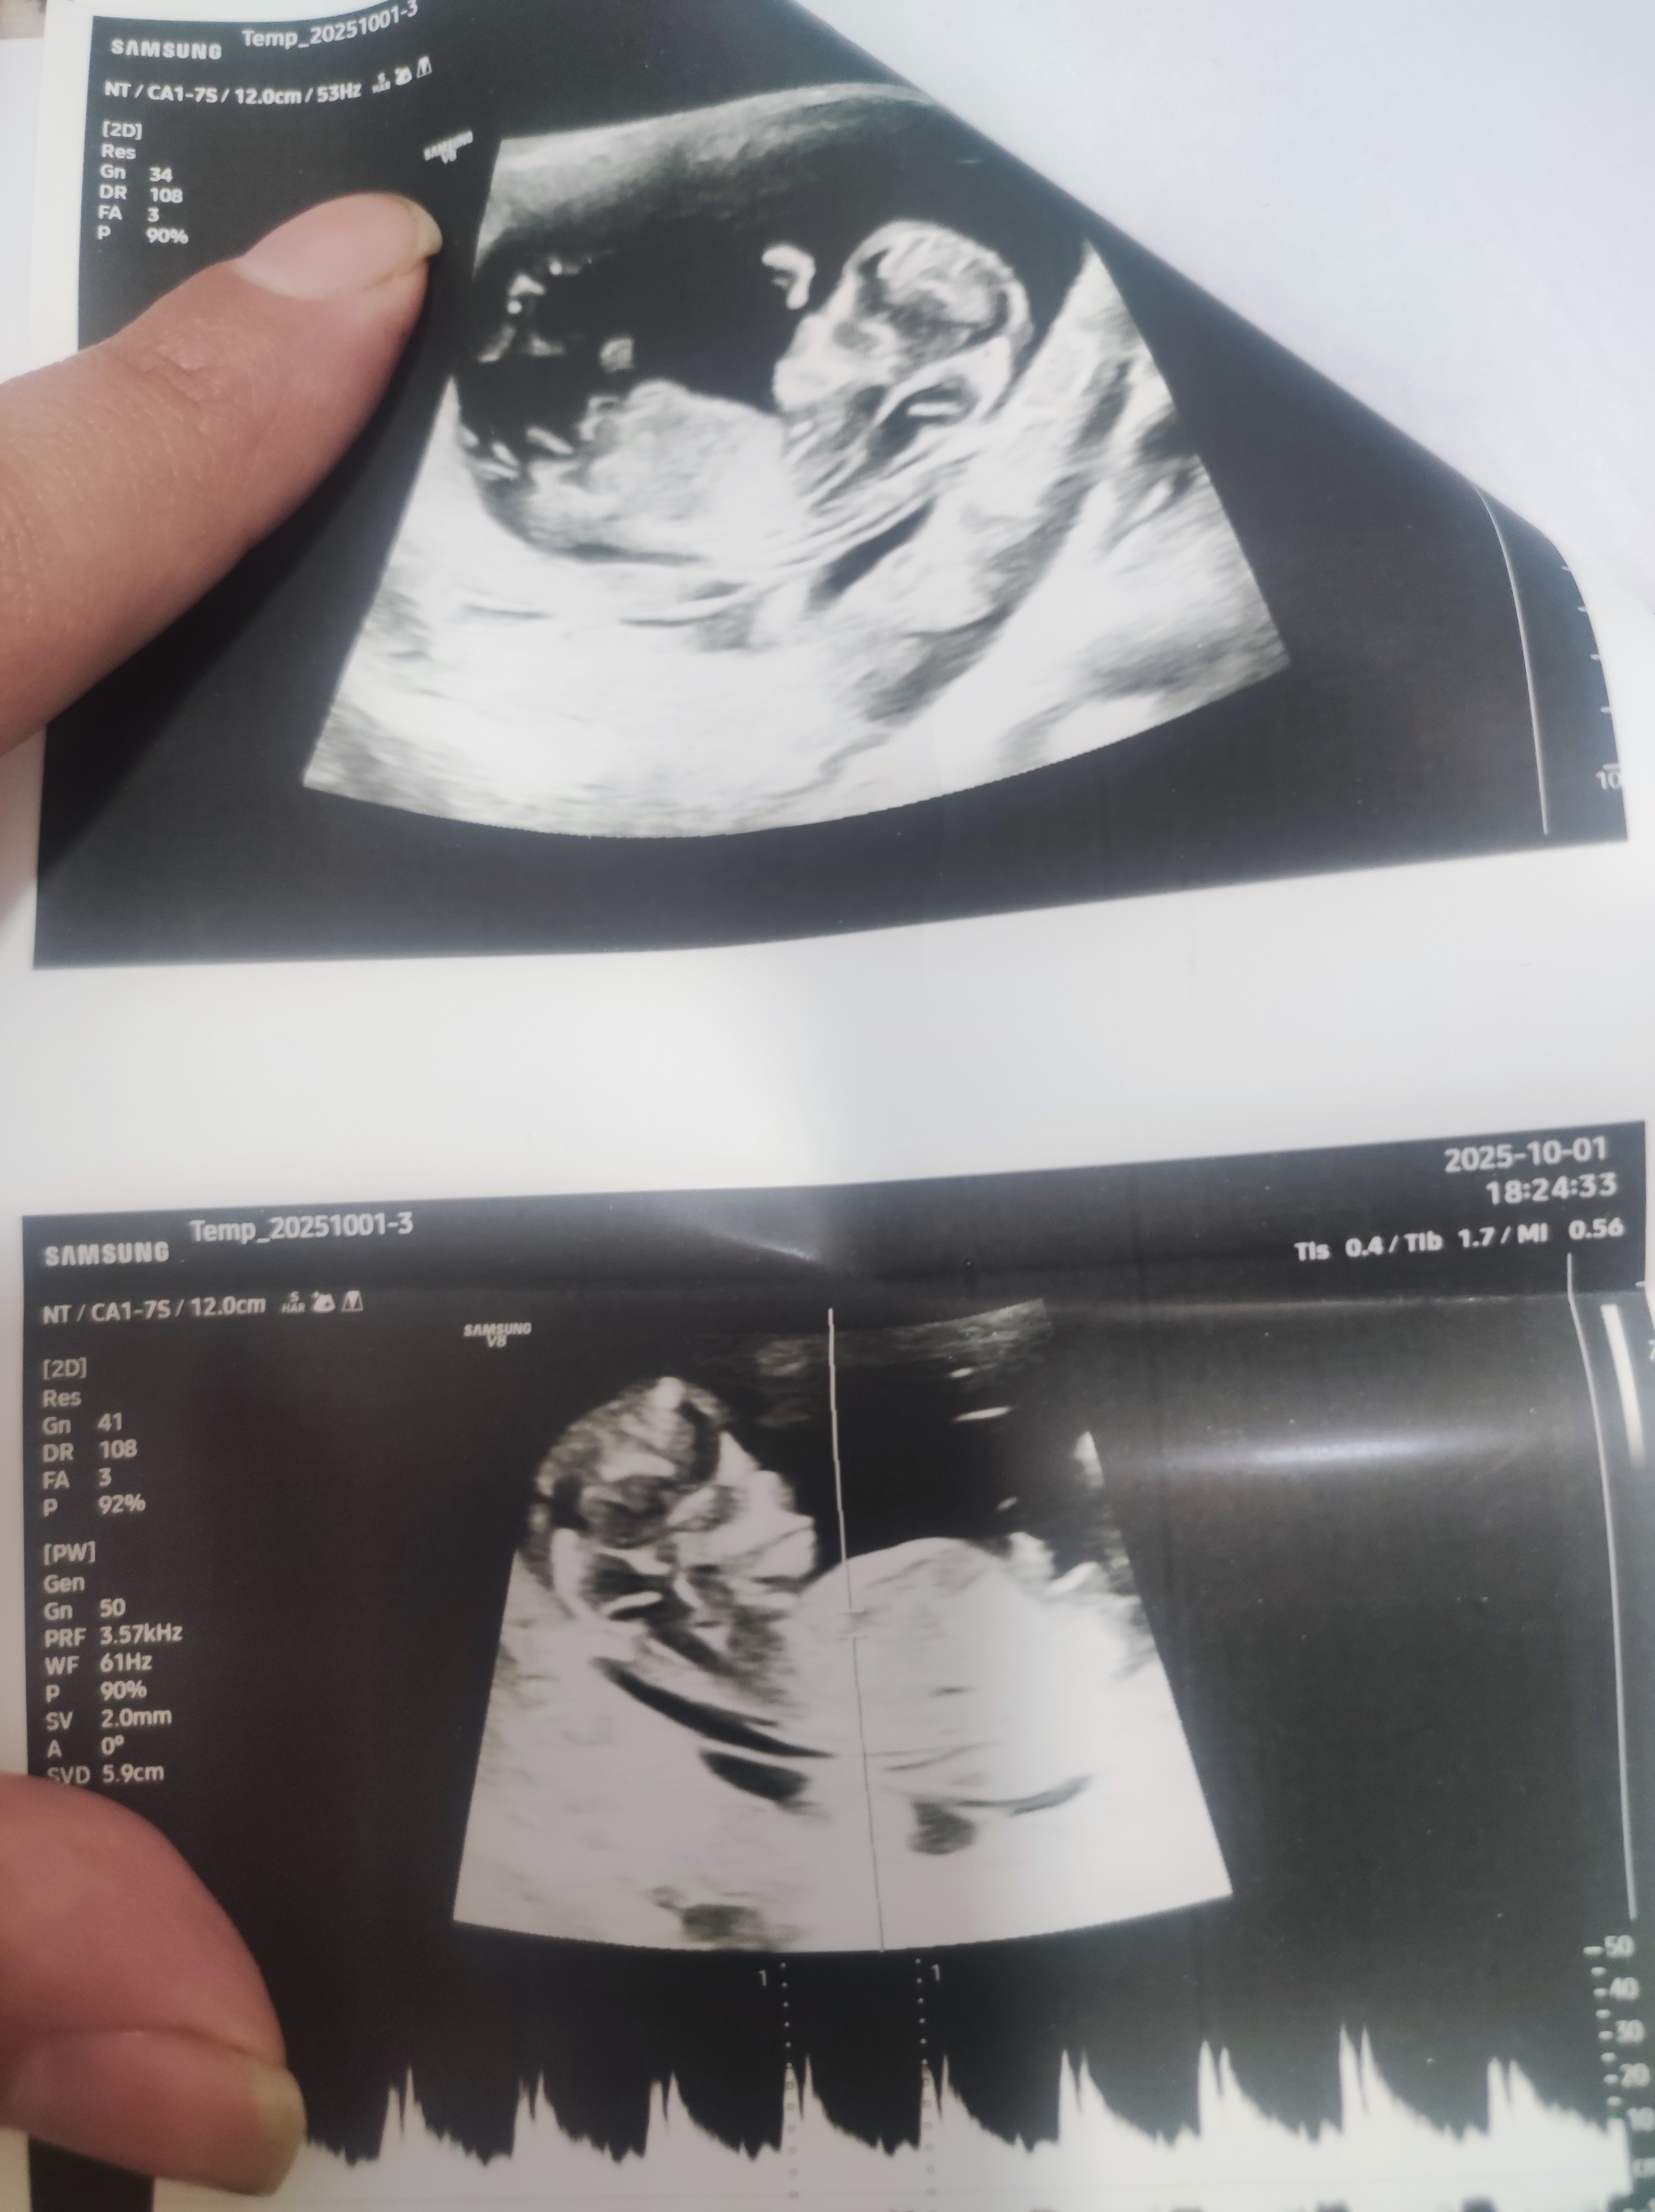

اقدام1404 مدیر استارتر عضویت: 1401/11/17 تعداد پست: 1299 دکترم اصلا خوب نبود عکس درستی هم بهم نداد عزیزم میگه عکس واضح نیست وزاویه نوب مشخص نیست اما میگه با توجه ب جمجمش میگه دختره اما گفت باز اصلا مطمان نیستم چون عکس واضح نیست

اقدام1404 مدیر استارتر عضویت: 1401/11/17 تعداد پست: 1299 دکترم اصلا خوب نبود عکس درستی هم بهم نداد ولی خودم احساس میکنم اون نقطه نوب مشخصه و شبیه پسره

sedna96 عضویت: 1396/08/30 تعداد پست: 9392 @sedna96 عزیزم سلام میشه جنسیت بچمو بگین سلام عزیزم خدا حفظش کنه از رو عکس اولی احتمالا پسره

اقدام1404 مدیر استارتر عضویت: 1401/11/17 تعداد پست: 1299 سلام عزیزم خدا حفظش کنه از رو عکس اولی احتمالا پسره ممنونم گلم خدا کنه خودشم احتمال داد پسر باشه دیگه نمیدونم